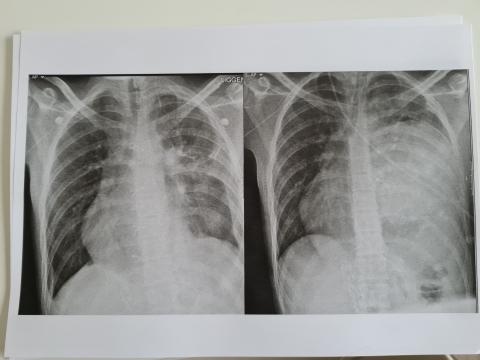

Vrijdag was even een slechte dag voor Max en de terugval had te maken met een gedeeltelijke klaplong. De linkerlong heeft al die tijd in de verdrukking gezeten en had wat moeite om te wennen aan de nieuwe ruimte. Door de medicatie is ook het extra vocht in de long nu afgenomen en zit er alleen nog wat vocht rondom de linkerlong maar dat kan geen kwaad op dit moment. Max is ook al een paar keer uit bed geweest en kan al goed zelfstandig rond lopen. Hij laat de chirurgen versteld staan van zijn herstel en de kracht om dingen te ondernemen. Dit komt ook doordat hij zich nu waarschijnlijk zoveel beter voelt nu de tumor niet meer op zijn longen en hart drukt. Hij kan nu ook makkelijker ademen wat erg fijn is. Nu zal zijn longcapaciteit nooit zo worden als bij een gezond iemand maar het is al vele malen beter dan het was en het is even afwachten hoeveel last hij hier in de toekomst van zal ondervinden. Morgenochtend komen de chirurgen weer even kijken en hopelijk mag hij dan al naar huis toe. Thuis herstellen is toch een stuk prettiger en als hij maar voldoende rust pakt kan hij bijna alles weer doen. Hoe het vervolg eruit komt te zien en of hij nu echt kanker vrij is weten we op dit moment nog niet. Hopelijk horen we hier in de loop van volgende week meer over. Hierbij nog even een foto van voor en na de operatie.